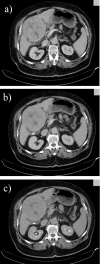

Hepatocellular carcinoma is a major health issue, ranked the fifth most common tumor and currently being responsible for a third of the cancer-related deaths globally, with an ever-increasing number of fatalities. Current advances in contrast-enhanced imaging techniques such as contrast-enhanced ultrasonography, multi-detector computed tomography and diffusion-weighted magnetic resonance imaging are improving the rate of hepatocellular carcinoma diagnosis. Contrast-enhanced ultrasonography has widely become the first choice in liver tumor assessment, as it is faster, simpler and safer than other forms of diagnostic imaging. On the other hand, cross sectional computed tomography is frequently employed when a hepatic formation is suspected of malignancy and allows a more accurate characterization of lesions through multiphasic multi-detector computed tomography technology. Diffusion weighted magnetic resonance imaging represents another addition to the wide range of diagnostic and prognostic techniques available for patients with hepatocellular carcinoma and is currently regarded as one of the best tools for the characterization of these lesions. Furthermore, groundbreaking biomarkers for hepatocellular carcinoma are being discovered, although alpha-fetoprotein remains one of the most frequently used serum test in the early stages. Nonetheless, further advances are required for the detection of small liver carcinomas.